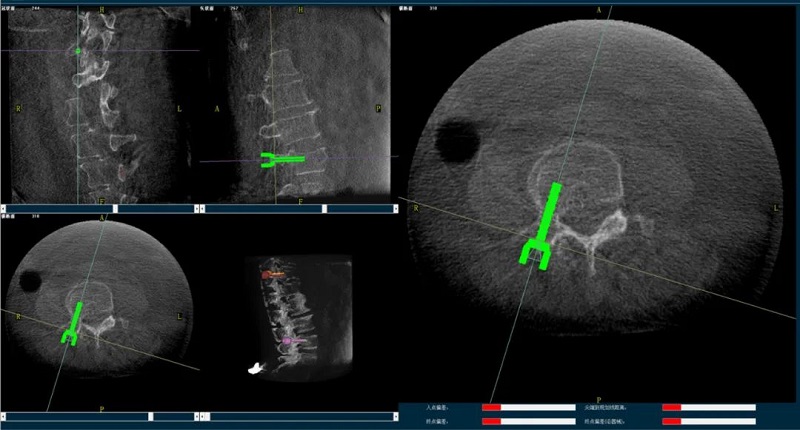

(2)醫生制定個性化的手術方案,在機器人導航界面上進行路徑規劃;

(3)根據設定好的的位置和入針方向,植入引導針;